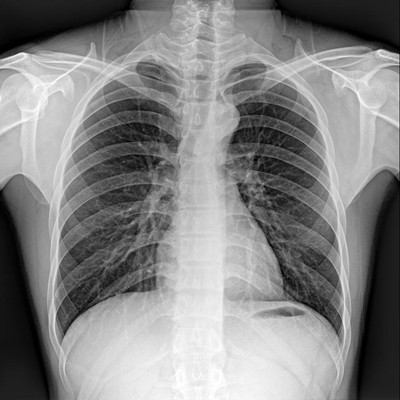

●大尺寸非晶硅平板探測器。

●探測器可以大范圍轉(zhuǎn)動,大尺寸有效探測面積,可滿足人體多部位攝影需求。